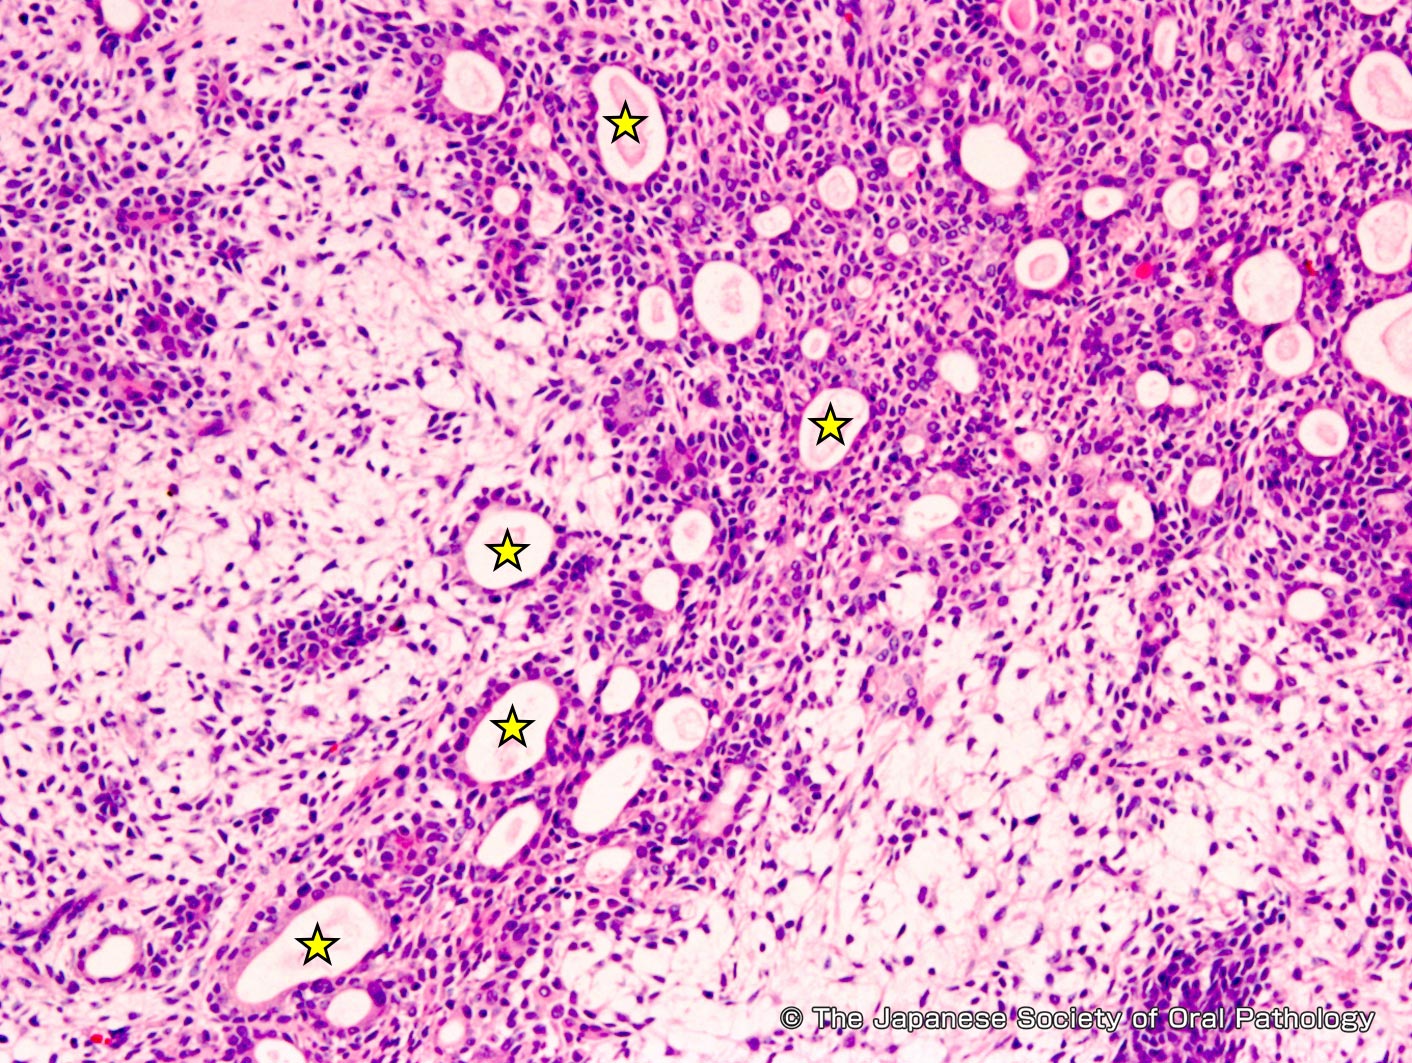

多形性腺腫由来癌 (CXPA) は、まれなタイプの唾液腺癌です。手術と放射線療法が最も一般的な治療選択肢です。

CXPAは、多形腺腫と呼ばれる非癌性腫瘍から発生します。多形性腺腫は最も一般的なタイプの唾液腺腫瘍です。これらの腫瘍のうち CXPA になるのはほんのわずかです。

CXPA はまれであり、ほとんど理解されていませんが、多形性腺腫と呼ばれる良性腫瘍から発生します。多形性腺腫は以下から構成されていると考えられています 45%~75%唾液腺腫瘍のこと。このうち CXPA になるのはほんのわずかです。

CXPAを他の種類の唾液腫瘍と区別するには、細針吸引が必要です。組織サンプルは研究室に送られ、医師は細胞の種類と特定の遺伝子マーカーを調べることができます。